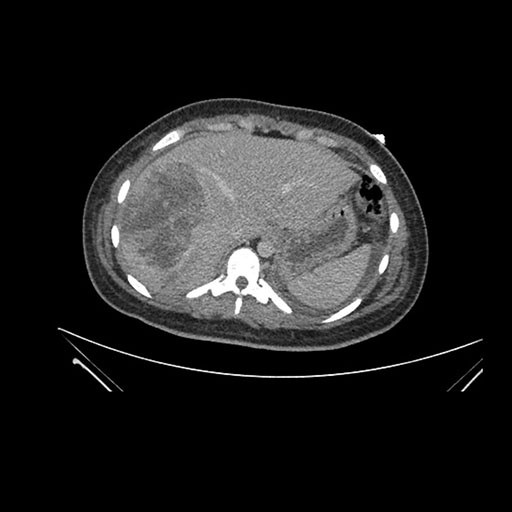

Imaging Analysis

Look through the patient's CT scan to identify any areas of concern for the necessary procedure.

Axial Arterial